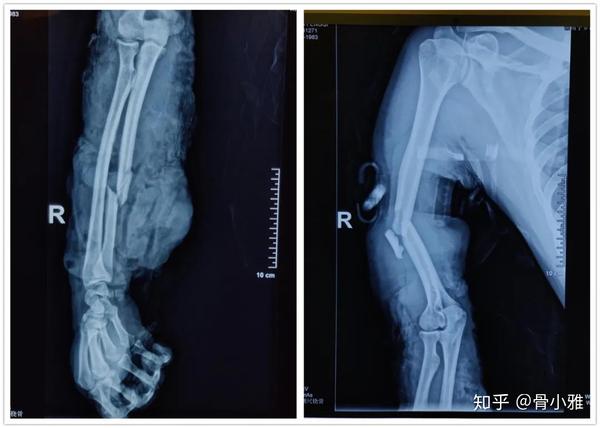

医院检查是右手臂右肱骨骨折,有两张图,帮忙看看?

图片尺寸600x800

术后第1天,患者右上肢伸腕活动正常,感觉正常,桡神经未受损伤